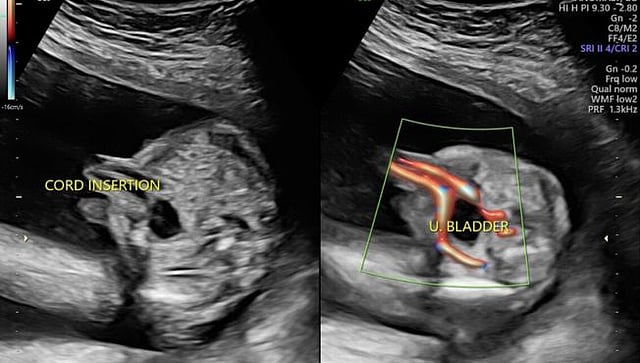

पुणे : गर्भवतींना झिकाची लागण झाल्यास आणि बाळापर्यंत संसर्ग पोहोचल्यास जन्मजात दोष निर्माण होण्याची शक्यता असते. त्यामुळे गर्भवती महिलेला १८ ते २४ आठवड्यांदरम्यान अॅनॉमली स्कॅन करण्याचा सल्ला दिला जातो. महापालिके अंतर्गत ८००० गर्भवती नोंदणीकृत असून त्यांच्या अॅनॉमली स्कॅनसाठी केवळ २ मशीन उपलब्ध आहेत.

गर्भधारणेच्या वेगवेगळया टप्प्यांमध्ये बाळाचा विकास पाहण्यासाठी सोनोग्राफी केली जाते. त्यामध्ये एनटी स्कॅन आणि अॅनॉमली स्कॅनला विशेष महत्त्व असते. गर्भवतींच्या नेहमीच्या तपासणीमध्ये या दोन्ही स्कॅनचा समावेश असतो. झिकाच्या पार्श्वभूमीवर अॅनॉमली स्कॅनला विशेष महत्व आहे.